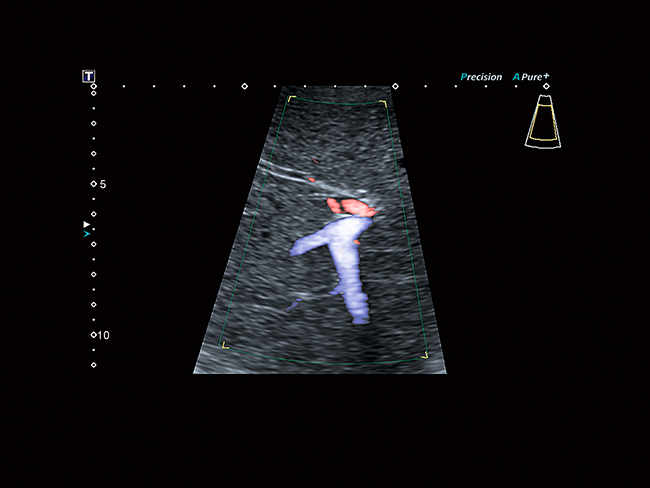

Превосходное разрешение и чувствительность

Усовершенствованный динамический поток (ADF) поднимает цветную допплеровскую визуализацию на совершенно новый уровень пространственного разрешения. Позволяет исследовать мелкую сосудистую сеть с беспрецедентной точностью и детализацией.

Видя невидимое

Превосходная микрососудистая визуализация (SMI) расширяет диапазон видимого кровотока для визуализации микрососудистого кровотока с высокой частотой кадров, повышая диагностическую достоверность при оценке поражений, кист и опухолей.